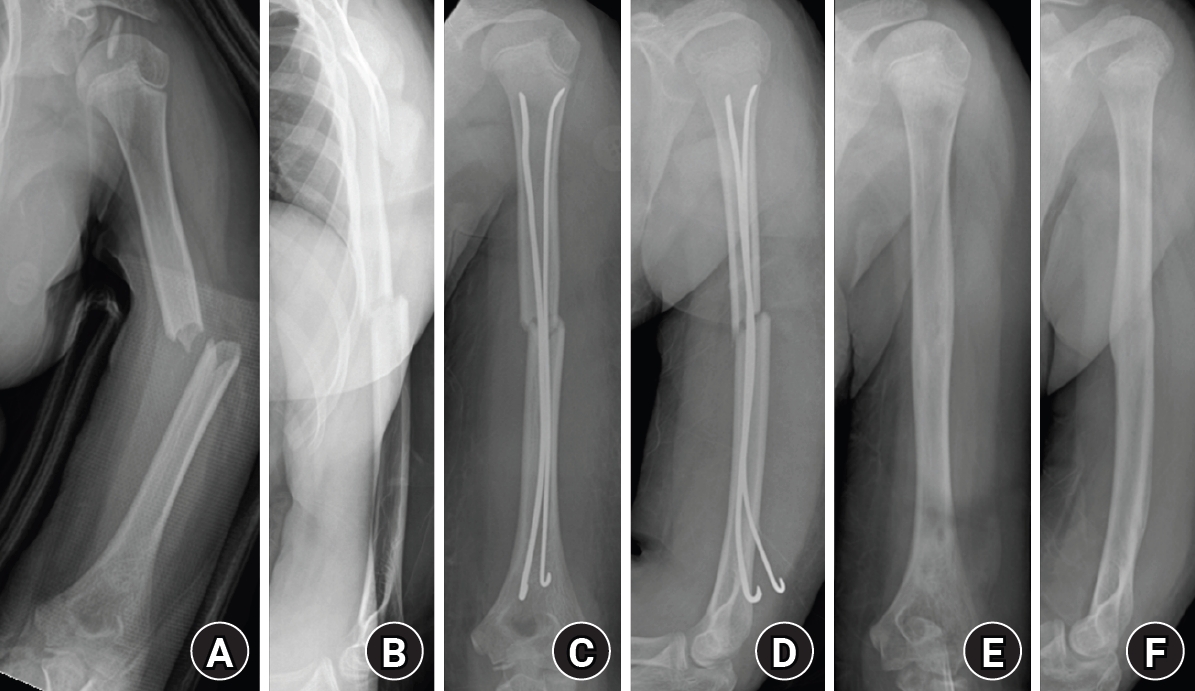

A single or double prebent titanium elastic nail (diameter, 2.0–3.0 mm) was chosen, with a diameter approximately one-third of the narrowest portion of the medullary canal [8]. In smaller humeri, the available canal diameter and posterior entry approach sometimes limited the maximal nail size, so a single nail was used to avoid excessive force during insertion. When the canal width allowed, two nails were inserted to achieve optimal end-point divergence and three-point elastic fixation. Proper alignment and rotational stability were confirmed under fluoroscopic control. After satisfactory reduction and fixation were achieved, the nail was cut and impacted beneath the posterior cortex to prevent soft-tissue irritation. Postoperatively, the arm was supported in a simple sling for comfort. Early gentle shoulder and elbow motion was initiated within the first postoperative week, and full range of motion (ROM) was allowed once radiographic callus formation was evident. All implants were removed after radiologic union was achieved (Fig. 2).

Fig. 2.

Radiographs of a representative case demonstrating successful bone healing following elastic stable intramedullary nailing fixation. (A, B) Preoperative anteroposterior and lateral radiographs showing a midshaft humeral fracture. (C, D) Immediate postoperative radiographs demonstrating satisfactory fracture alignment and stable fixation with elastic nails. (E, F) Follow-up radiographs obtained after implant removal showing complete bone union and restoration of normal humeral alignment.

Fig. 2. Radiographs of a representative case demonstrating successful bone healing following elastic stable intramedullary nailing fixation. (A, B) Preoperative anteroposterior and lateral radiographs showing a midshaft humeral fracture. (C, D) Immediate postoperative radiographs demonstrating satisfactory fracture alignment and stable fixation with elastic nails. (E, F) Follow-up radiographs obtained after implant removal showing complete bone union and restoration of normal humeral alignment.